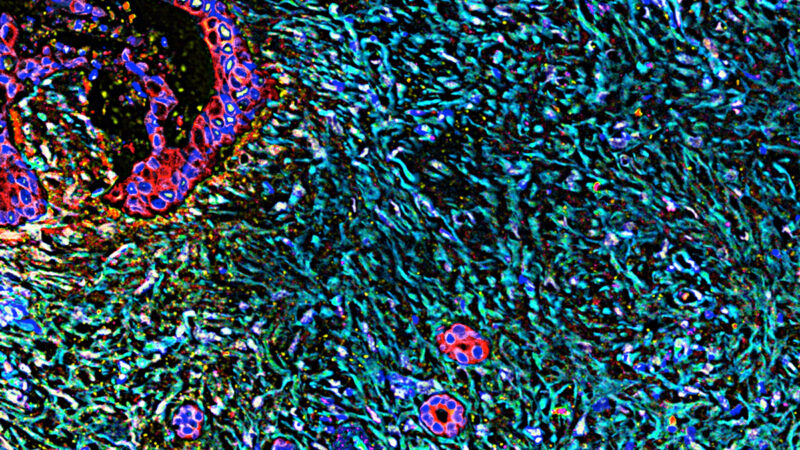

Foto: En Codiak Biosciences, los investigadores están estudiando la ingeniería de los exosomas,…